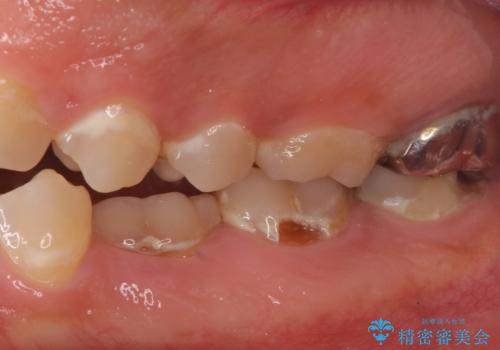

- 口の中を予算の範囲内でできるだけきれいにしたいとのことで来院された患者様です。

矯正治療と虫歯治療を組み合わせてご提案しましたが、ご予算との兼ね合いで虫歯治療のみを行うこととなりました。

奥歯は十分な歯の高さがなかったため、クラウンをかぶせる前に歯周外科治療で歯の高さを出しています。

歯科に通うようになってから磨き残しの状態も改善されていきました。